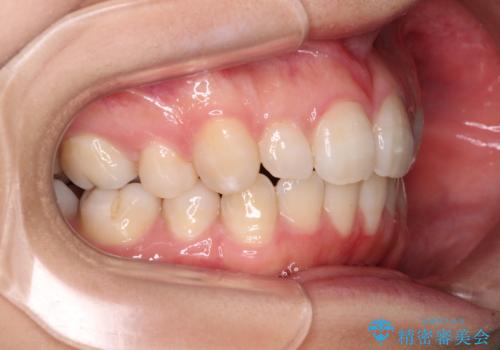

- 30代女性

- 下顎前歯を中心に、以前行った矯正治療の後戻りが気になるとのことで来院された患者様です。

後戻りは軽度であったため、インビザライン・ライトにて治療を行うこととしました。

治療途中で出産をされたため、通院が困難となりましたが、インビザライン・ライトでの治療可能期限である2年以内に無事に治療を終えることができました。